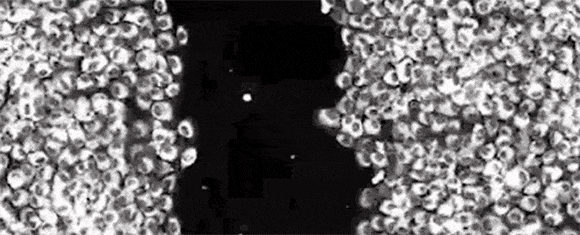

これを調べるために、2017年、英ケンブリッジ大学の研究者は、皮膚の細胞(繊維芽細胞)の反応が時間帯によってどのように異なるのかを調べることにした。

怪我をすると、繊維芽細胞は損傷を受けた部分に移動して、「コラーゲン」という修復プロテインを作り出し、組織の修復を助けようとする。

しかし、こうした機能が作動するためには、「アクチン」というタンパク質が必要になる。

したがって、これが十分にない部位では、繊維芽細胞は本来の機動性を発揮することができない。

そして、そのアクチンのレベルは概日リズムによって決められている――つまり、こうした皮膚の細胞も昼夜のサイクルにしたがって活動しているのである。

研究チームが繊維芽細胞を培養し、そこに傷をつけてみたところ、夜を再現した環境で傷をつけたときの治りは、繊維芽細胞の反応速度の違いのために、昼よりも遅いことが確認された。